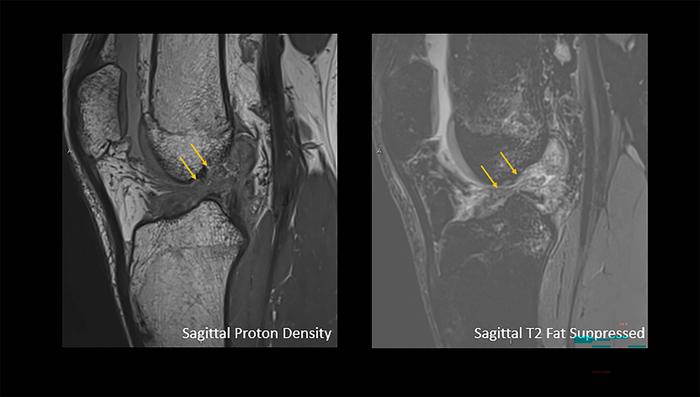

Complete anterior cruciate ligament rupture (IMAGE)